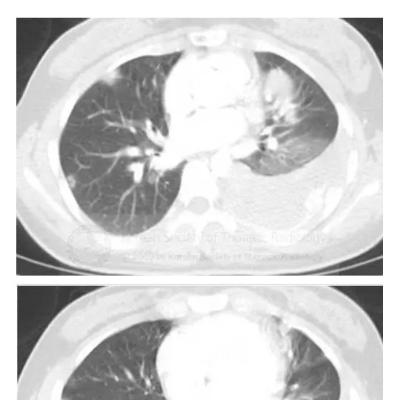

男,45岁,咳嗽,咳痰1个月,发热,盗汗,体重下降5公斤,肺结核病史30年.右肺下叶病变性质待查?